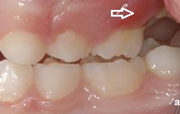

Esimese jäävmolaari ektoopiline lõikumine

) Röntgenülesvõte. Ülemise esimese jäävmolaari lõikumine on takistatud 2. piimamolaari tõttu

Ravijärgne seis. Jäävhammas on täielikult lõikunud.